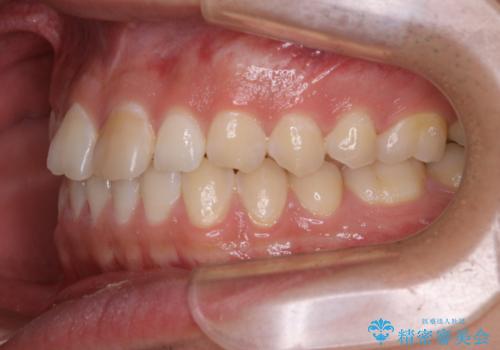

矯正を考えている方のPMTC

- 矯正治療を考えていて、歯科医院が久しぶりのためまずはクリーニングしたいとのことでした。PMTC60分コースを行いました。